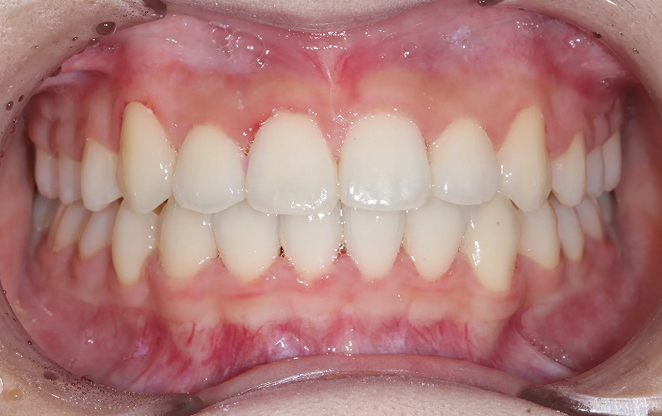

Before

After